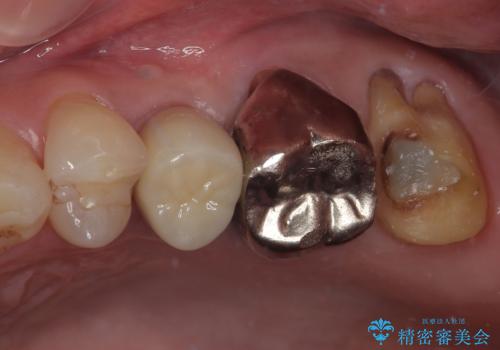

- 銀歯がとれたのでやり替えたいとのことで来院された患者様です。何度も同じ部位の銀歯の脱離を繰り返しており、メタルインレーの不適合も認めていたためオールセラミッククラウンにて補綴治療を行っていくことにしました。